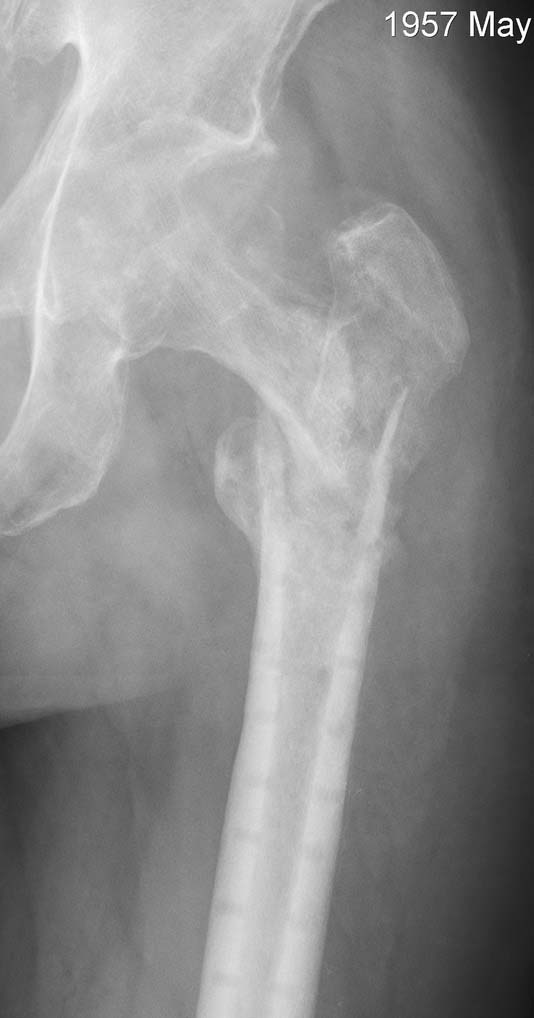

[Ortho] Несращение проксимального отедла бедра, дефект головки

Имя     : Ponomarev и1.jpg